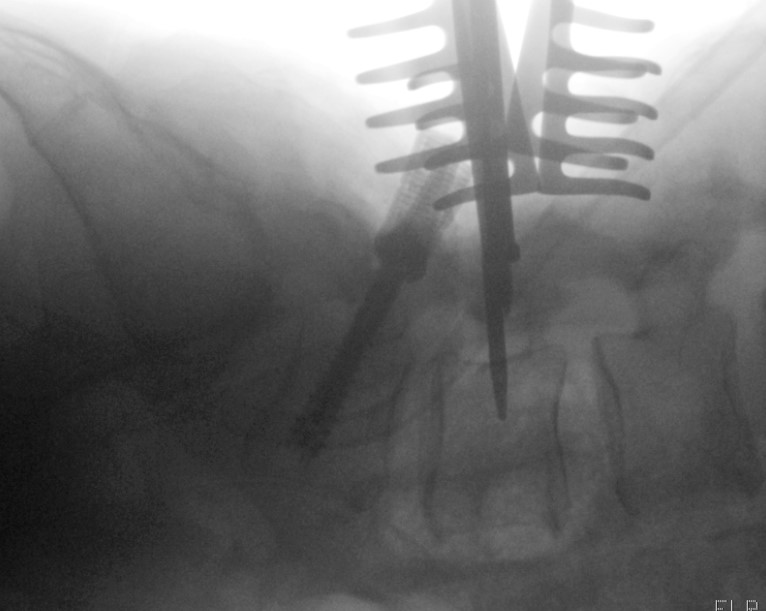

| placing-screw-in-L4.png | 2025-12-14 16:21 | 363K | ||